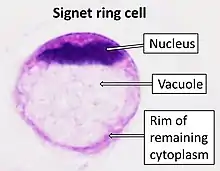

SRCCs are named due to their resemblance to signet rings, which result from the formation of large vacuoles full of mucin that displaces the nucleus to the cell's periphery.[16]